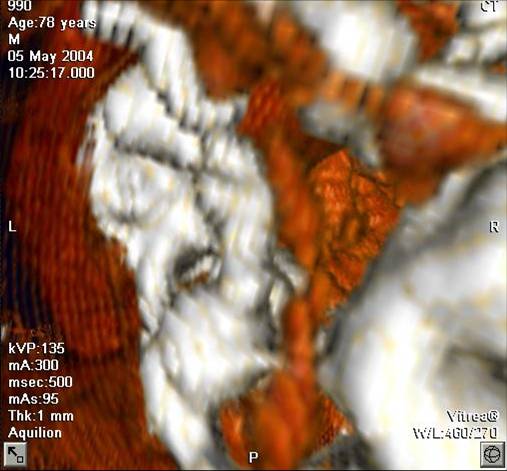

The non-invasive imaging modality of multi-detector computed tomography has dramatically evolved the last ten years and that is due to hardware and software developments. The newer generation of scanners allows increased spatial and temporal resolution that improves the clinical reliability giving further insights into the evaluation of coronary artery disease. Heart morphology imaging followed by studies of myocardial function and assessment of cardiac valves can be performed from the information derived from the data of the coronary artery examination. Also, the venous anatomy of the heart, coronary artery bypass grafts, stents, and cardiac tumors can be imaged and evaluated when necessary. For the beneficial use of this method, entrance criteria for different patient groups need to be set in order to allow improved outcome of multi-detector CT.